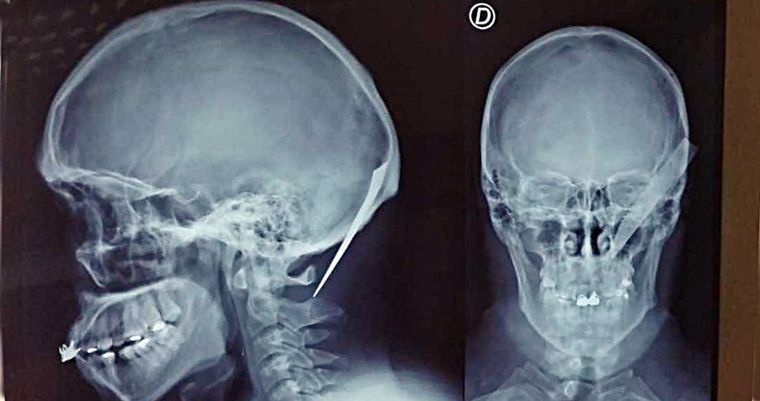

Los vecinos de Puerto Madryn, en Chubut, no dejan de asombrarse ante la valentía de un joven de 28 años. El hecho ocurrió el lunes por la noche en calle San Juan al 500 cuando un hombre fue abordado en su domicilio por cuatro personas de su familia que comenzaron a golpearlo brutalmente. En ese contexto, uno de ellos sacó un cuchillo y se lo clavó en la cabeza.

Luego, con el cuchillo aún en la cabeza, el joven de 28 años se dirigió hacia la comisaría donde fue auxiliado y trasladado al Hospital. Por fortuna, el arma blanca no había afectado zonas vitales y, luego de una operación para extraerlo de la cabeza, quedó fuera de peligro.